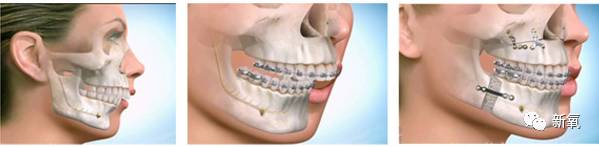

同样的道理,深覆盖、深覆合、龅牙嘴凸这些上颌过度发育的情况,也会明显影响下颌骨的发育。

所以我们常见的嘴凸、龅牙的例子,几乎都伴有下巴后缩、下颌短小等下颌骨发育不足的情况。

和地包天是一样的原理,在骨骼成型前,将其用外力引导到正确位置。利用牙槽骨的改建能力,让颌骨发育问题得到改善。

如果是比较严重的凸嘴,成年后就只能选择动骨(正颌)手术来解决这个问题了额··· 如果有下巴严重后缩的,还需要下颌的处理或隆下巴。